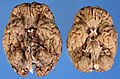

Neuropathological dissection (autopsy)

Brain fixation after removal: Usually 14 days

- Check brain for:

- Lesions

- edema (might be not visible but tissue is softer than normal)

- hemorrhage

- Discolorations

- Asymmetry (midline shift)

- herniation (subfalxial, uncal, tonsillar)

- vascular abnormalities

Atrophy: widespread sulci, often seen in neurodegenerative diseases

Brown discolorations indicating demyelinisation